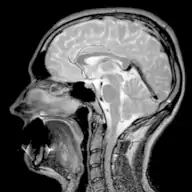

- Магнитно-резонансная томография